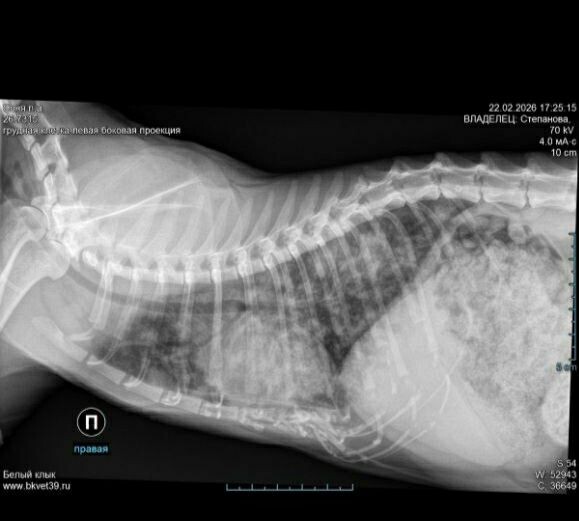

📣 Вчера Светлана свозила СОНЮ на Рентген и замену катетера

📣 Вчера Светлана свозила СОНЮ на Рентген и замену катетера!🙏

Сразу данные ушли лечащему врачу и нам скорректировали лечение.🙏